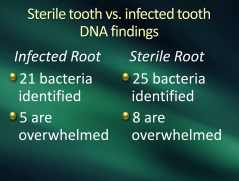

I dream that dentistry will finally discover

hundreds of microbes living under cover

I dream we’ll use our DNA

to chase the anaerobes away